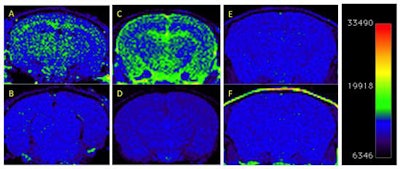

T1-weighted MRI of amyloid deposits in mouse models, before and four days after IV injection of nanoparticle MR agent. A 2D spin-echo sequence was used. Coronal 2D slices of the brain through the cortex and hippocampus are shown. Window level and window width are set identically for each pair of images: A-B, C-D, E-F. (A) TetO/APPswe-ind mouse, 15 months old, amyloid precursor protein (APP) production suppressed until 6 weeks of age by doxycycline in diet. (B) Preinjection scan of same mouse. (C) Tg2576 mouse (APPswe), 9 months old, and (D) preinjection scan of same mouse. (E) Tg2576 mouse injected with untargeted (nonamyloid-binding) particles. (F) Nontransgenic sibling of E, injected with amyloid-targeted particles. Total signal was mapped to a rainbow color map using Osirix software; the range from the predominant blue background to green foreground represents a >2X signal increase, and the range from green to yellow a further 2X increase. Nine-month-old Tg2576 mice show a different pattern of labeling compared with older TetO/APP mice, suggesting slow clearance from the cerebrospinal fluid in the Tg2576 example. Images are consistent with 6/6 animals in TetO/APPswe-ind group and 2/6 in the Tg2576 APP+ group. Subsequent immunohistochemical measurements showed that only these 2/6 Tg2576 animals had amyloid pathology, while the other 4/6 did not, consistent with the MRI signal. Reprinted from the Journal of Alzheimer's Disease, Annapragada et al, "A novel liposomal nanoparticle for the imaging of amyloid plaque by magnetic resonance imaging," Vol. 52:2, pp. 731-745, 2016, with permission from IOS Press.